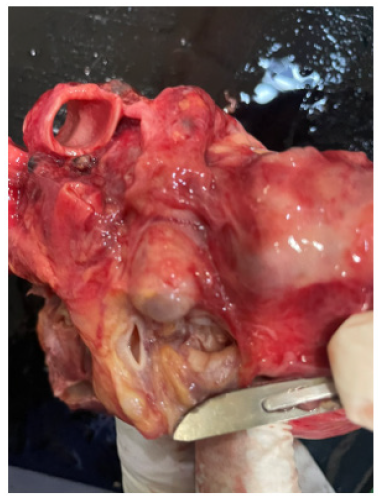

Figure 9a-9b are post-mortem examination of cut section of left ventricle. The forceps pointed the aneurysm of Sinus of Valsalva; it was attached to posterior cusp of aortic valve. And it was close to left coronary ostia. The myocardium of the whole left ventricular was hyperemic indicating very extensive myocardial infarction.

Figure 9a: Post-mortem exasmination of cut section of left ventricle and the forceps pointing the aneurysm of Sinus of Valsalva attached to posterior cusp of aortic valve. The myocardium of left ventricular is hyperemic.

Figure 9b: Post-mortem examination of cut section of left ventricle and the forceps pointing the aneurysm of Sinus of Valsalva attached to posterior cusp of aortic valve. The myocardium of left ventricular is hyperemic.